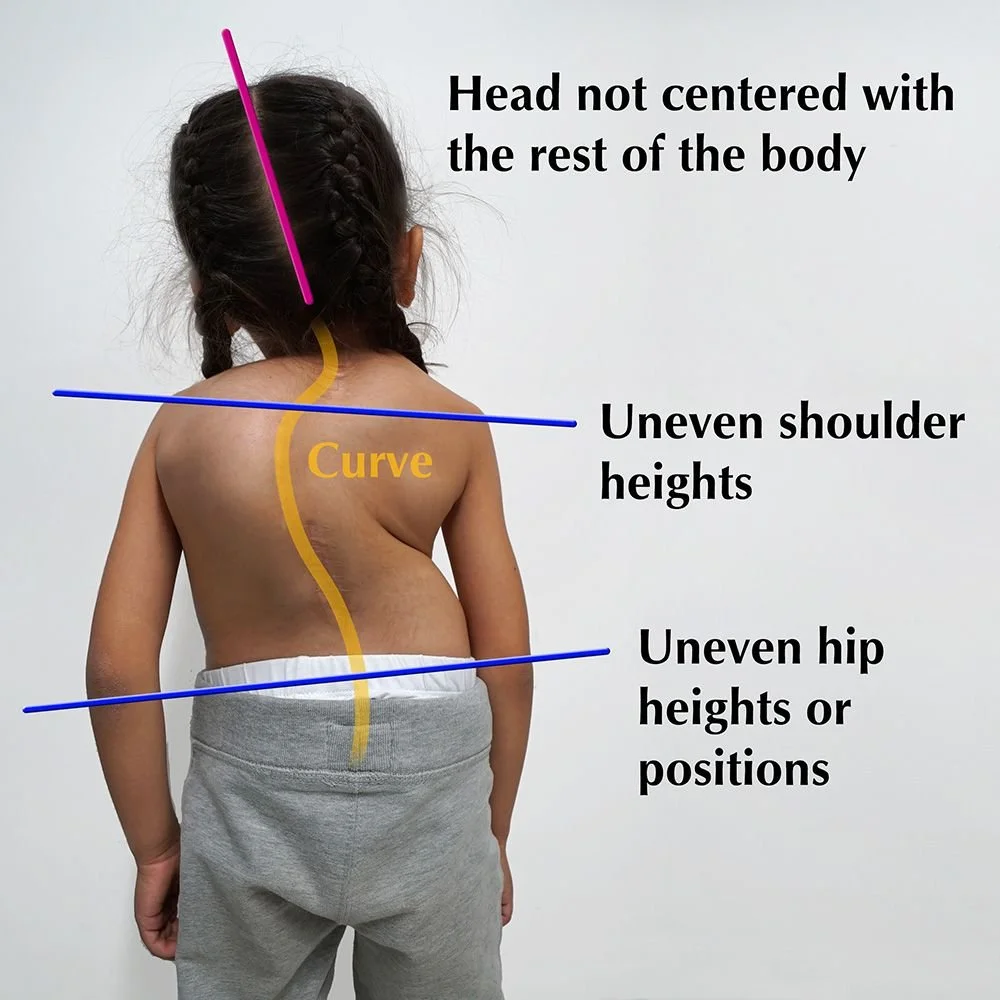

- explain/ Define Scoliosis.(સ્કોલિયોસીસ ને વ્યાખ્યાયિત કરો).

સ્કોલિયોસીસ એ એવી કન્ડિશન છે કે જેમાં સ્પાઇનનું લેટરલ કરવેચર થાય છે.એ કાં તો લેફ્ટ અથવા તો રાઇટ સાઇડ પર જોવા મળે છે.

નોર્મલ ચાઇલ્ડ ની સ્પાઇન એ સ્ટ્રેઇટ હોય છે પરંતુ સ્કોલીઓશીસ વાળા ચાઇલ્ડ ની સ્પાઇન નું કર્વેચર એ લેટરલ થયેલું હોય છે.

સ્કોલિયોસીસ માં સ્પાઇન એ C- શેપ અથવા S – શેપ થાય છે.

explain the Clinical manifestation/sign and symptoms of the Scoliosis(સ્કોલિયોસિસ લક્ષણો તથા ચિન્હો લખો).

- અનઇવન શોલ્ડર (એક બાજુનો શોલ્ડર ડાઉન થતું હોય તથા એક બાજુનું સોલ્ડર એ અપ થવો.).

- સ્પાઇનલ કરવેચર થવું.

- અનઇવન પેલ્વિસ .

- એક લેગ એ ડાઉનવડ તથા એક લેગ એ અપ થાય છે.

- બેક પેઇન.

- ટીંગલીંગ તથા નંબનેસ.

- પરમનેન્ટ ડિફીરમીટીઝ થવી.

- થાક લાગવો.

- સ્વાસ લેવામાં તકલીફ પડવી.

- માઇટ્રલ વાલ્વ વ પ્રોલેપ્સ થવા.